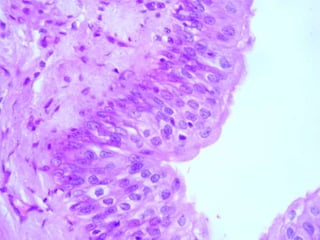

Epitelio de transición ,  polimorfo  o  urotelio El urotelio se podrá encontrar en dos estados, uno se denomina  estado contraído  y el otro  relajado . En el estado contraído (vejiga vacía) hay  muchas ca-pas celulares , las células apicales se  hacen globosas . Cuando el epitelio se estira al llenase la vejiga (estado relajado) se llegan a distinguir  sólo dos capas  de células.

Todas las células de este epitelio presentan finas prolongaciones mediante las cuales están ancladas a la membrana basal. A estas células se las denomina  células en forma de raqueta  y el glucógeno almacenado perinuclear es utilizado para poder obtener energía y lograr este reordenamiento a medida que cambia el volumen vesical.

Vejiga En los  cortes histológicos  de rutina obtenidos de la vejiga vacía las células epiteliales superficiales suelen ser cuboides y protruir dentro de la luz. Con frecuencia se describen como abombadas o "en cúpula" por la curvatura de su superficie apical, las células apicales son globosas y esta es una diferencia muy importante para no confundir al urotelio de la vejiga con el epitelio plano estratificado de la piel.

Epitelio de transición, polimorfo o urotelio El urotelio se podrá encontrar en dos estados, uno se denomina estado contraído y el otro relajado . En el estado contraído (vejiga vacía) hay muchas ca-pas celulares , las células apicales se hacen globosas . Cuando el epitelio se estira al llenase la vejiga (estado relajado) se llegan a distinguir sólo dos capas de células.

Todas las célulasde este epitelio presentan finas prolongaciones mediante las cuales están ancladas a la membrana basal. A estas células se las denomina células en forma de raqueta y el glucógeno almacenado perinuclear es utilizado para poder obtener energía y lograr este reordenamiento a medida que cambia el volumen vesical.